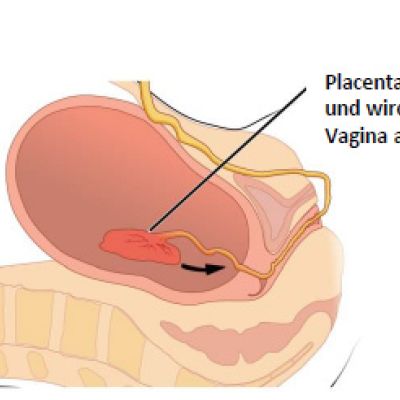

Schematische Darstellung einer Geburt in 3 Phasen: